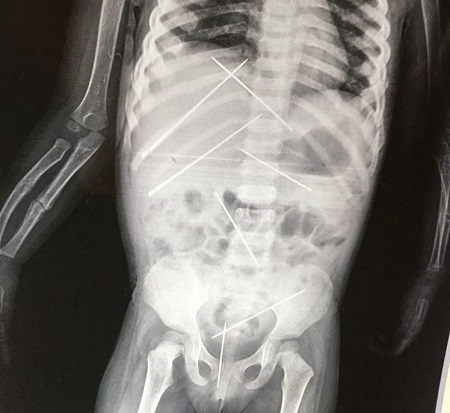

An X-ray shows the needles that were shoved into the young girl’s body (Picture: SWNS)

A man performing black magic has ended up leaving as many as seven long pins inside the body of a very young girl. These are the horrifying X-ray pictures showing seven two-inch long pins stuck inside a three-year-old girl by a man accused of torturing her using ‘black magic’.

Doctors discovered there were several needles inserted in her abdomen and she had a broken arm.

Seven pins had to be surgically removed from her body (Picture: SWNS)